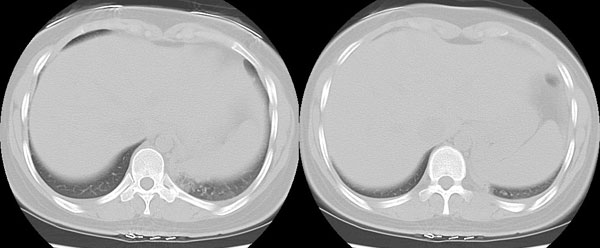

女性,25岁。反复咯血3年,再咯10天。外院x线胸片示:肺炎?支扩?

ct所见:左肺下叶基底段见大片状毛玻璃样改变,其内可见扩张细支气管。

ct诊断:考虑支气管扩张合并感染.

ct所见:左肺下叶基底段见大片状毛玻璃样改变,其内可见扩张细支气管及血管纹理影。后接正常描述。

ct诊断:左肺下叶支气管扩张伴出血。

胸部ct平扫所见:胸廓两侧欠对称,左侧略小,胸壁骨质结构完整。左肺下叶后、外基底段

见大片状毛玻璃样淡薄影,边缘渐淡,其内可见多个环形小囊状影。余肺野清晰,

肺纹理规则,气管支气管通畅,内壁光滑。心脏、大血管大小、形态、密度未见

明显异常,胸膜不厚、光滑,纵隔内未见明显肿大淋巴结。

诊断意见:左肺下叶大片状毛玻璃样淡薄影考虑支气管扩张伴出血。